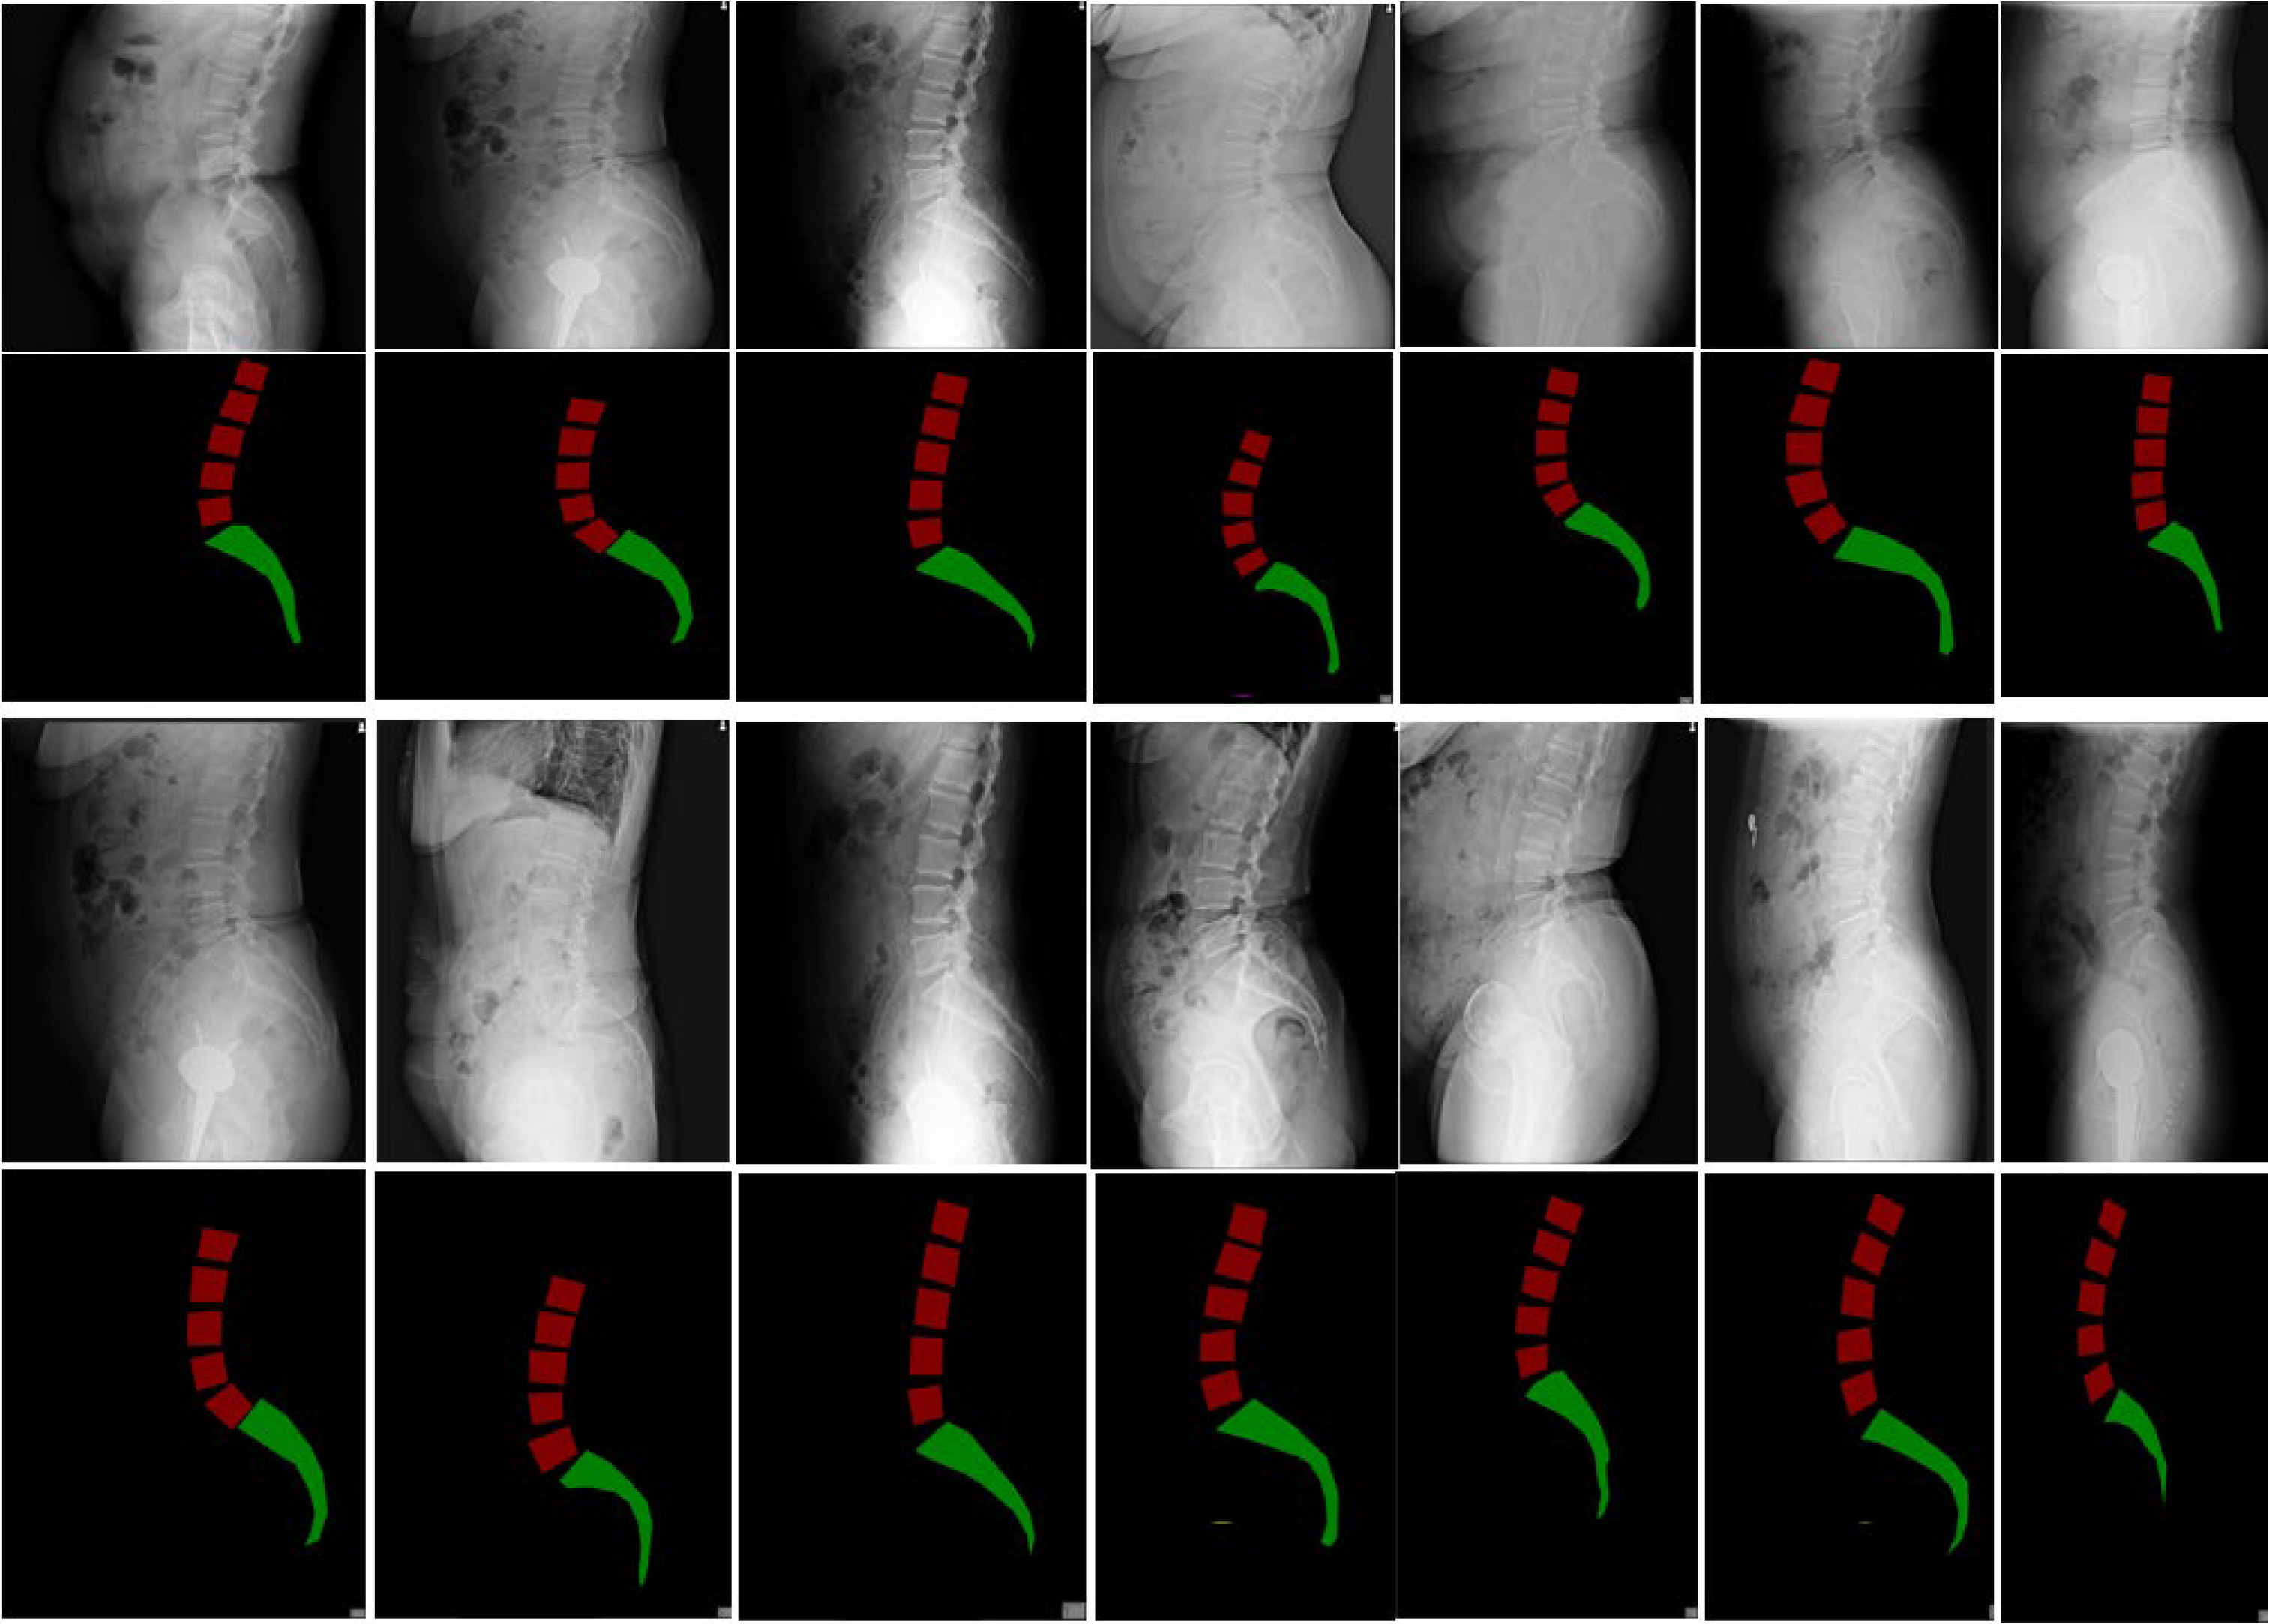

All selected 3300 lumbar images in the hospital dataset were collected via the Digital Imaging and Communications in Medicine (DICOM) system. After converting the DICOM images into JPG format, three professional spinal specialists annotated the images using LabelMe. The annotation included (1) marking the lumbar spine from L1 to L5 with bounding boxes and (2) marking the entire sacrum with points (Figure 1). After randomizing the data, the hospital dataset was split into the training, validation, and test sets in a 7:2:1 ratio, with the 1100 images in the external dataset used as the test set (Table 1). The average age and gender composition of patients in each dataset showed no significant differences. The distribution of GR-classified lumbar spondylolisthesis (LS) grades across the datasets is presented in Table 2.

Figure 1. Illustration of the vertebra labeling approach.